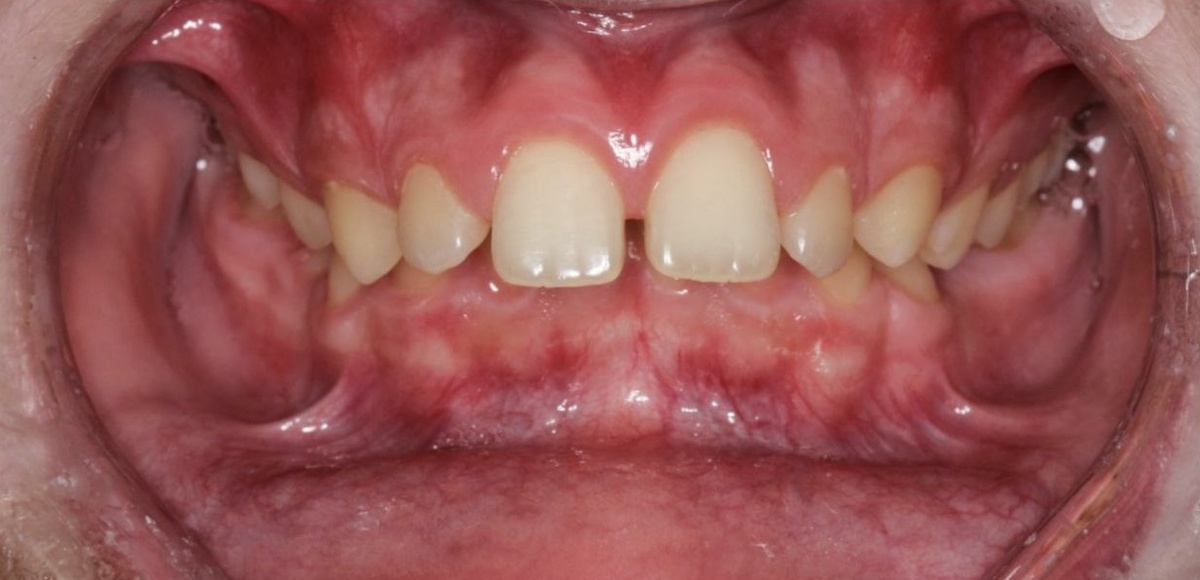

Итак, изначальная ситуация в полости рта достаточно сложная:

• Дистальный прикус

• Глубокая окклюзия

• В профиль видно, что губы не смыкаются, резцы торчат и сильно отклонены вперед.

Чем это плохо помимо эстетики? Глубокий прикус ведет к сколам зубов и травматизациям десны.

При несмыкании губ они постоянно обветрены и травмированы резцами.